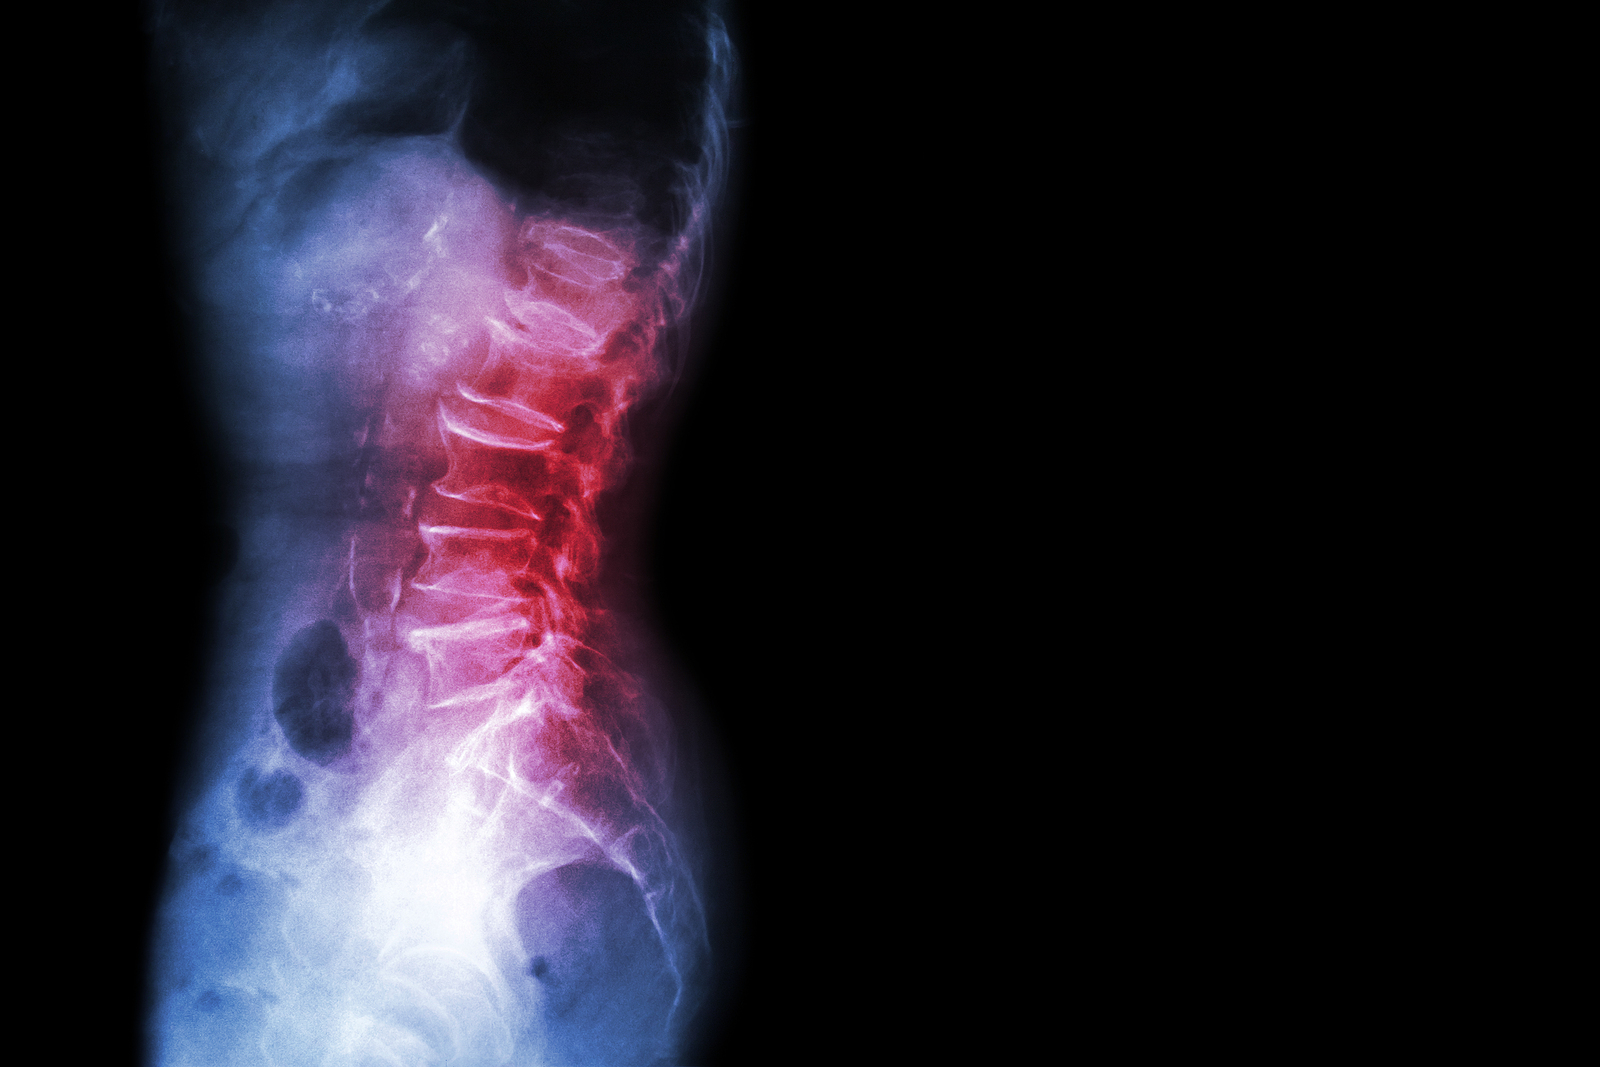

What Makes Up the Lumbar Spine?

The human spine is made up of 24 spinal bones, called vertebrae, as well as the sacrum and the coccyx. The sacrum is a triangular bone near the bottom of the spine and the coccyx is more commonly known as the tailbone.

Vertebrae are stacked on top of one another to create the spinal column. The spinal column gives the body its form and helps sustain an upright position.

The lumbar spine—where pain is often experienced—is made up of five vertebrae positioned near the bottom of the spinal column. Doctors often refer to these vertebrae as levels L1, L2, L3, L4 and L5. The ‘L’ refers to ‘lumbar’. The lowest vertebra, L5, is connected to the top of the sacrum—a triangular bone at the base of the spine that is located between the two pelvic bones. Some people are born with an extra or sixth lumbar vertebra called L6. Having an extra vertebra doesn't usually cause physical problems.

X-rays

X-rays are usually the first test ordered before any of the more specialized tests are completed. X-rays use electromagnetic radiation to show problems with bones and can also reveal problems such as fractures, infections, or bone tumors. X-rays of the spine can give your doctor information about bone alignment and can demonstrate how much degeneration has occurred in the spine. Both alignment and degeneration can affect the amount of space in the neural foramina and between the discs, which subsequently impacts the nerves in the area. This is important information your health care professional can use to establish a treatment plan.